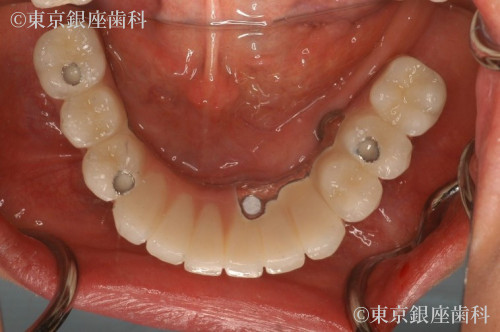

当日下顎は抜歯のみを行い、炎症が収まるまで義歯待機。上顎OPEから2か月後下顎4本埋入。仮歯を入れ噛み合わせを安定させた為、顎の変位も改善された。

抜歯即時埋入でインプラント治療を行い、その日のうちに仮歯を入れて短期間での大幅な審美、機能の回復をした。

口腔内の悩みを解決することでQOL(クオリティオブライフ:生活の質)を向上することに成功した。。